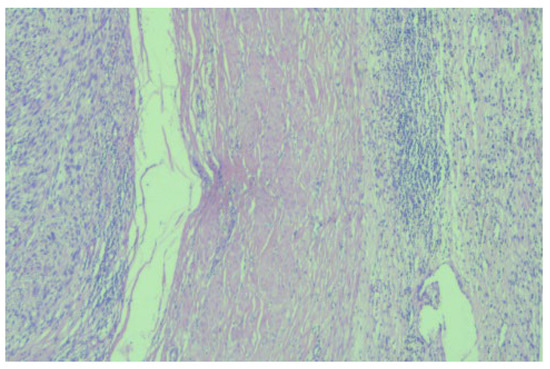

2. Case Report